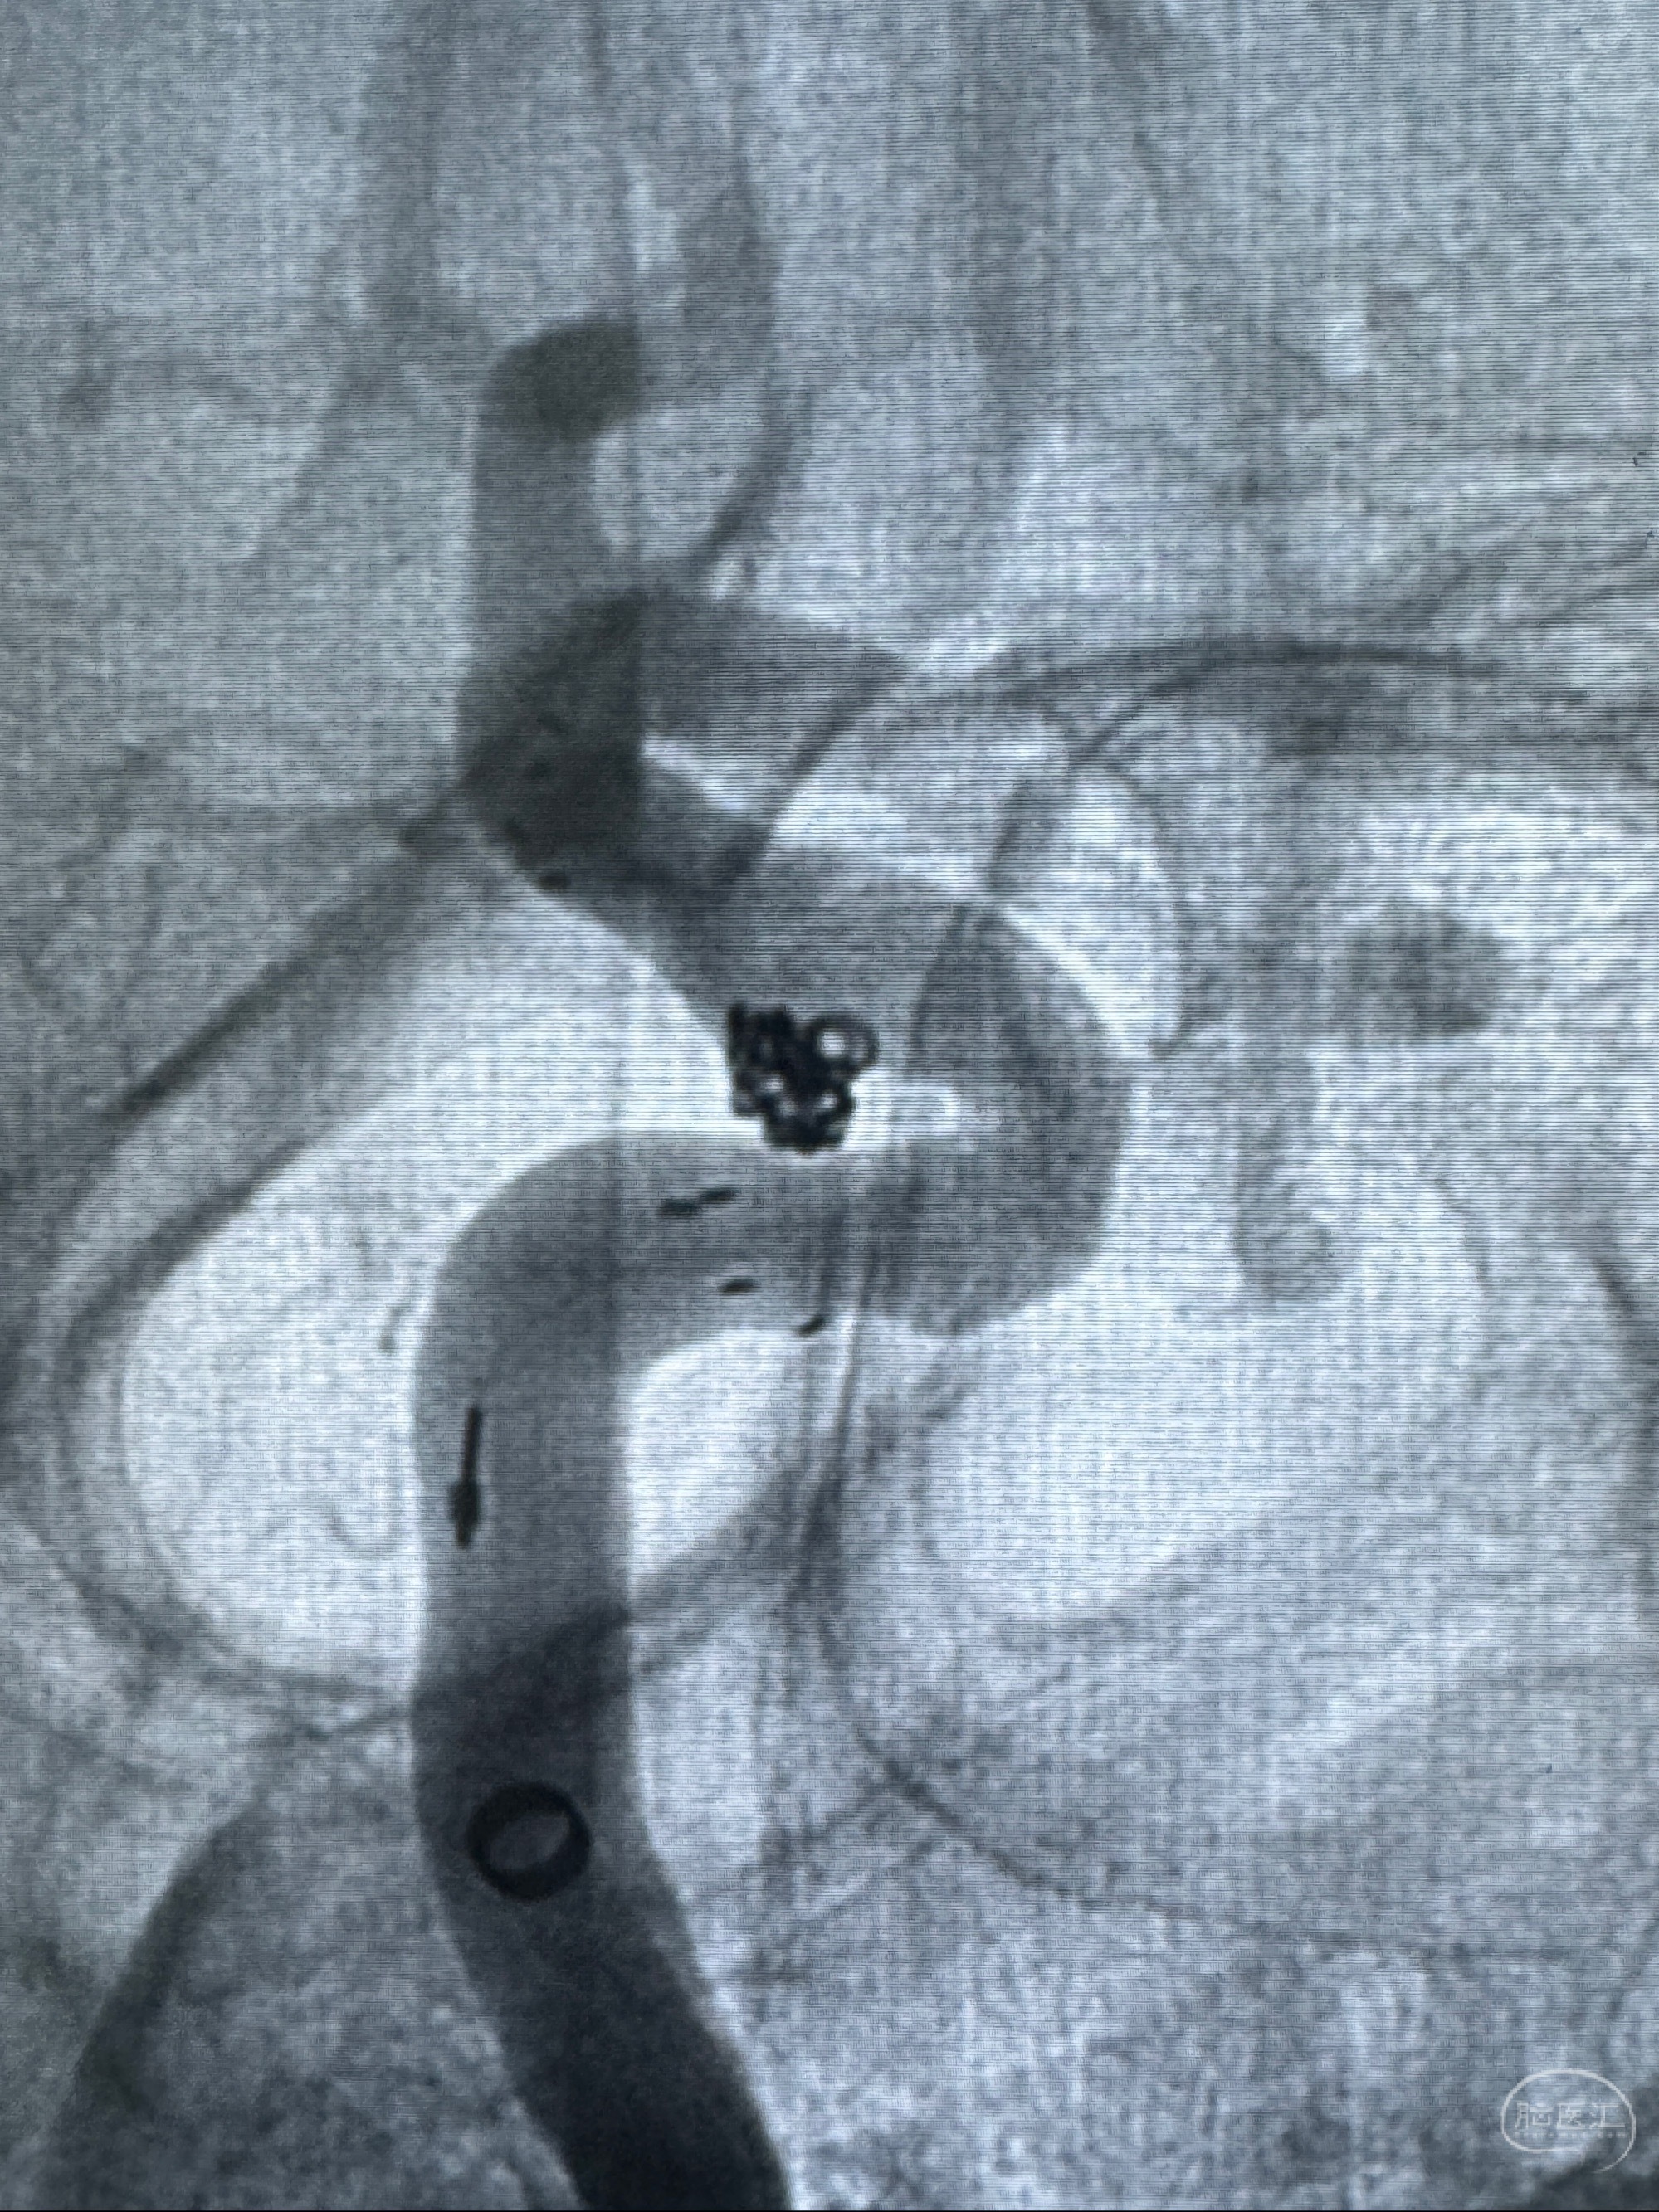

2023-11-13DSA:左侧颈内动脉眼动脉后壁动脉瘤

2023-11-29全麻下行NeuroformEZ4.5-20mm支架辅助栓塞

术后即刻CT